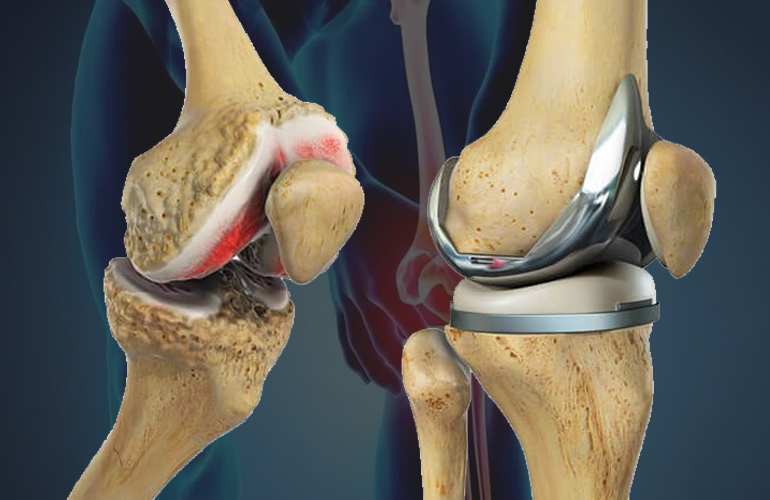

Joint replacement surgery is a highly advanced orthopaedic procedure in which surgeons remove damaged or worn-out joint surfaces and replace them with artificial implants. In doing so, they restore proper alignment and joint mechanics. These implants closely mimic natural joint movement and, as a result, restore smooth and pain-free function.

1. Total Knee Replacement (TKR)

Surgeons replace damaged knee joint surfaces with advanced prosthetic components. As a result, patients regain smooth knee movement and significant pain relief.